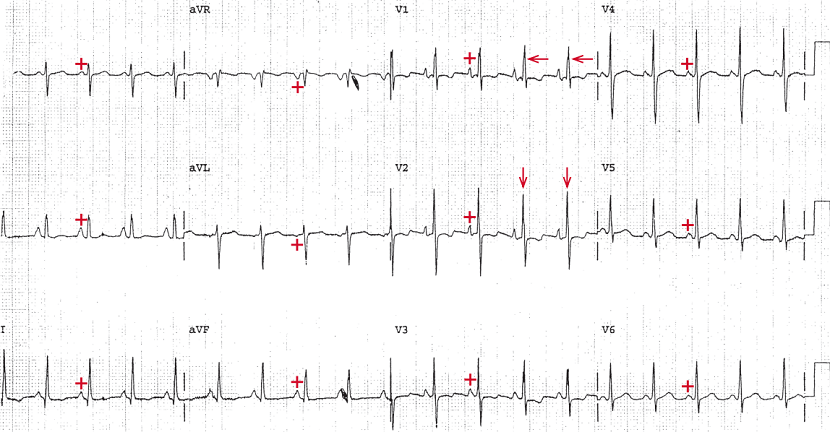

22岁女性硬皮病患者,主诉进行性劳力性呼吸困难。查体发现P2减弱,且有全收缩期杂音,在呼吸运动时发生变化,在胸骨左缘下段最清楚。常规心电图检查如图1。

心电图显示,心律规则,110次/分。每个QRS波前都有一个P波(+),PR间期恒定(0.16s)。P波在Ⅰ、Ⅱ、aVF和V4~V6导联为正向,且P波时限正常(0.10s)。所以是窦性心动过速。P波异常,在Ⅱ、aVF和V1~V2导联呈高而尖峰状。这样的P波形态是典型的肺型P波,是右心房肥厚的结果。这也可以称为右心房异常。

图2 心电图分析:窦性心动过速,右心房肥厚,右心室肥厚(RVH),电轴右偏,逆时针方向转位

QRS波时限正常(0.08s)。QT/QTc间期正常(300/410ms)。但是,QRS波形态异常。电轴右偏,在+90°和+180°之间(QRS波在Ⅰ导联为负向,在aVF导联为正向)。主要表现在V1导联R波偏高(←),即振幅超过7mm(7个小格)或者R/S>1。V1导联上高的P波加上电轴右偏和肺型P波(右心房肥厚)是右心室肥厚(RVH)的特征。此外,在V2导联(↓)上也有一个高的R波。虽然这可能是RVH导致的,但也可能表明电轴在水平面是逆时针方向转位。这可以通过膈下位心脏成像加以确认;右心室在前边,左心室在左侧。逆时针方向转位会出现提前转化,也就是说,左心室电势向前移位,而其在胸前导联发生得更早。